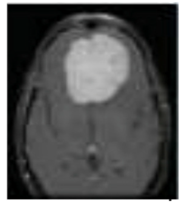

4. Experimental Setup

The REMBRANDT publicly available dataset, which is a publicly available database, was used to test the proposed method. The data set was partitioned into two parts: training and testing. Images of glioma tumors, meningioma tumors, pituitary tumors, and no tumors were included in both the training and testing sets. A total of 3100 images are taken, and the image dataset percentages for training and testing the proposed system framework were 80% and 20%, respectively. Thus, both a training set of 2480 images and a testing set of 620 images were used, and data pre-processing operations, such as brain stripping, were offered to improve the data description [40]. However, the 3100 images were like a combination of different grade (tumor) images in order to fine-tune the proposed model to obtain a better classification accuracy [41]. The performance assessment work was divided into four groups: glioma tumor, meningioma tumor, no tumor, and pituitary tumor. Figure 9 displays many instances of various tumors: (a) meningioma, (b) glioma, and (c) pituitary. Table 2 illustrates the total number of images that were used in the proposed system during the training and testing phases.

Figure 9.

Different types of tumors in the brain region from the REMBRANDT dataset. (a) Meningioma; (b) Glioma; (c) Pituitary.